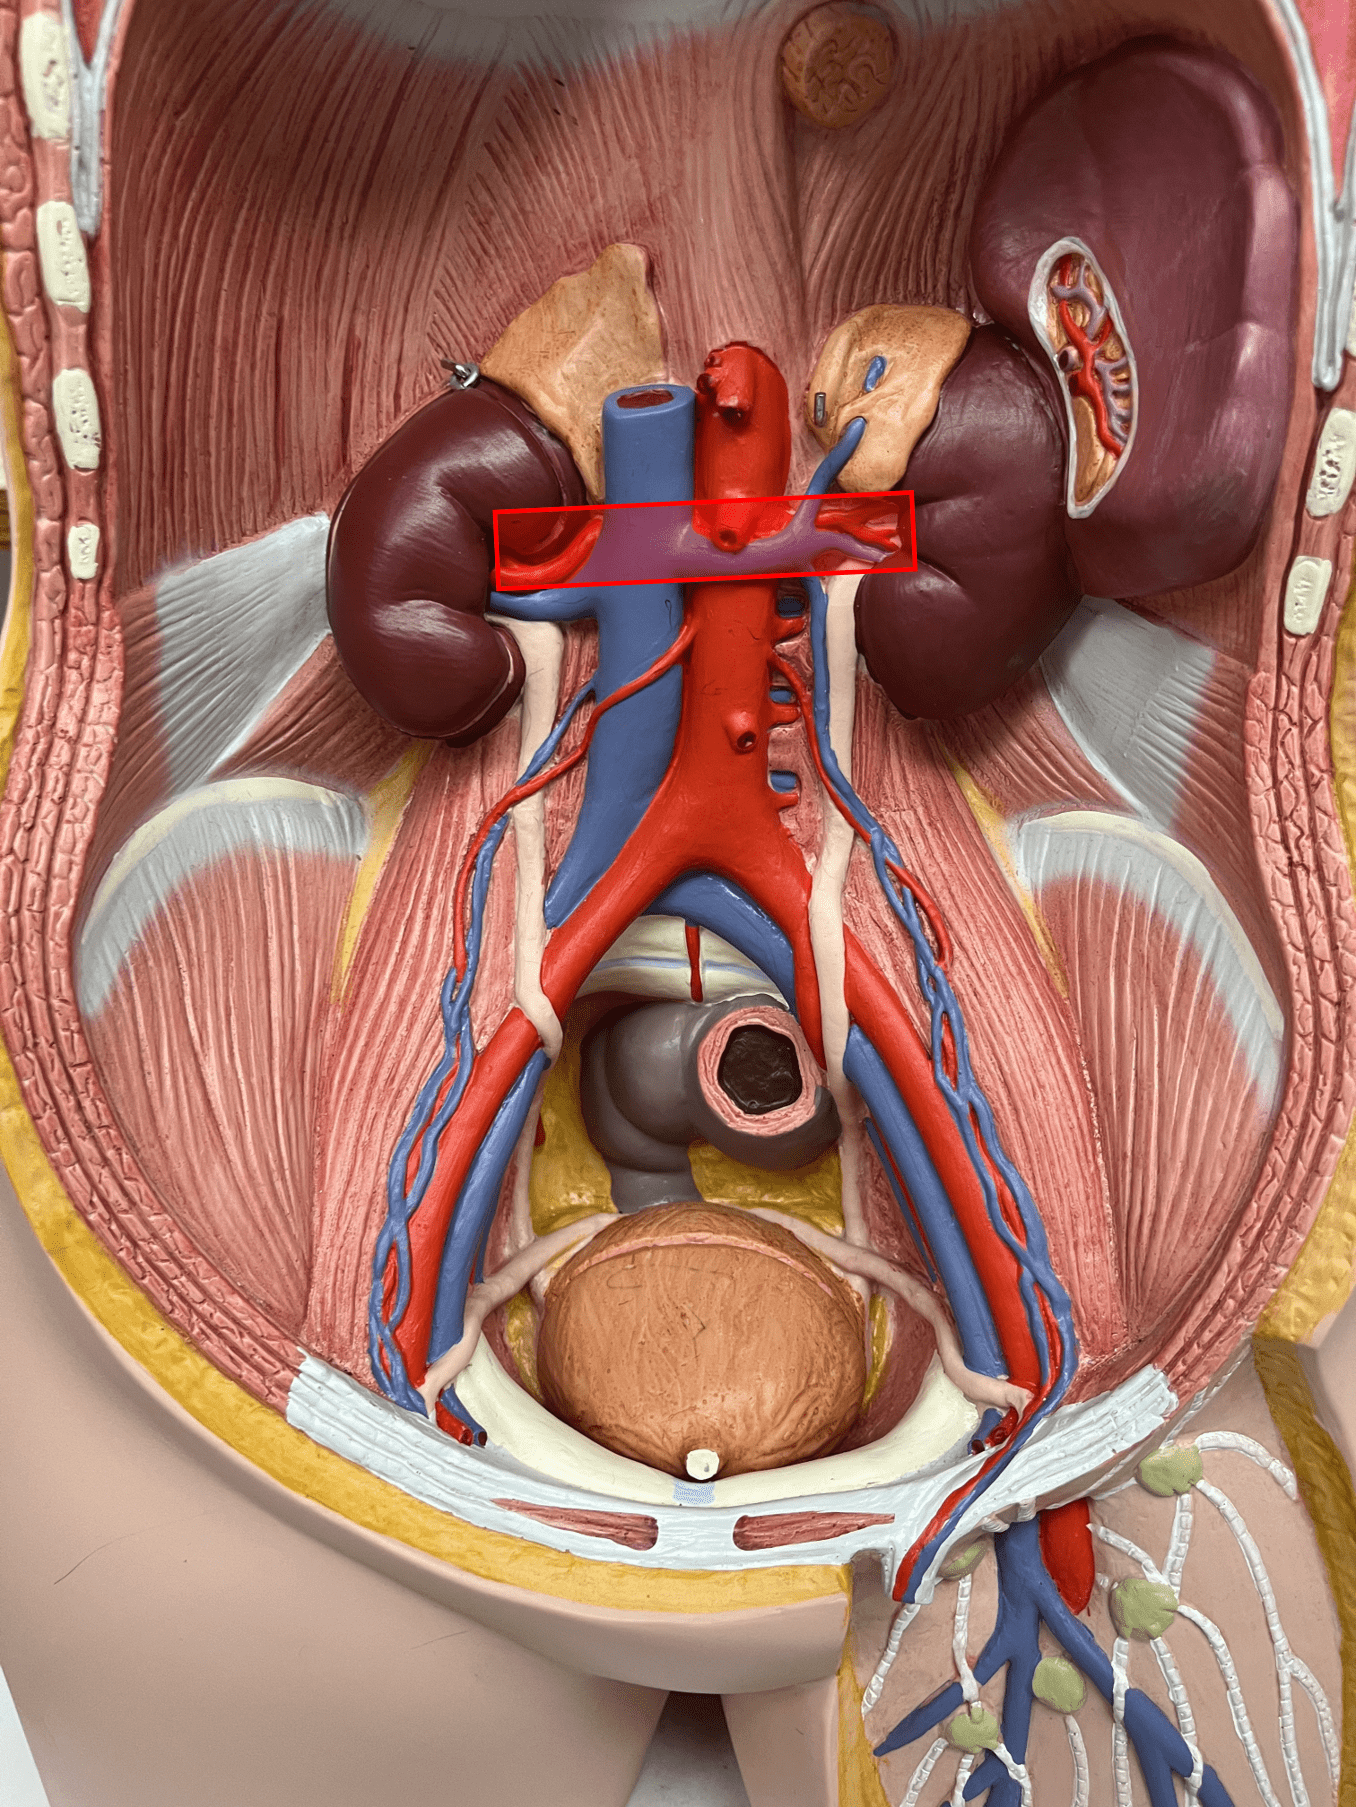

tunica media

7